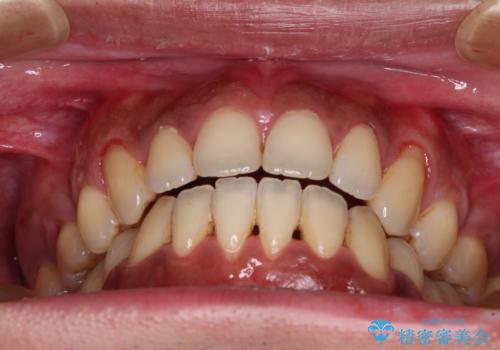

隙間が空いて突出した前歯を治したい ワイヤー装置による抜歯矯正

- 上下前歯の隙間と口元の出っ張った感じを気にして来院された患者様です。

上下の隙間は舌突出癖によるもので、またその癖により前歯が前方に出ている状態でした。

口元の出っ張りを改善するため、上下左右第一小臼歯4本を抜去し、ワイヤー装置にて矯正治療を行うこととしました。

舌の突出癖を改善するためのトレーニングを指導していましたが、なかなか改善することができず、ワイヤー装置を外してからも上下前歯に隙間ができやすい状況でした。